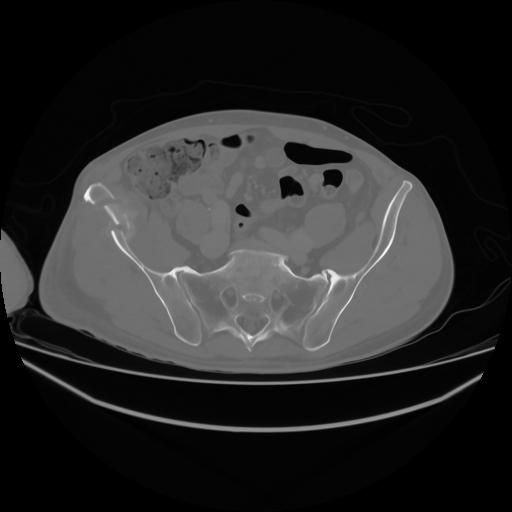

4 CUERPO,CE,Axial,3.0,CUERPO,,